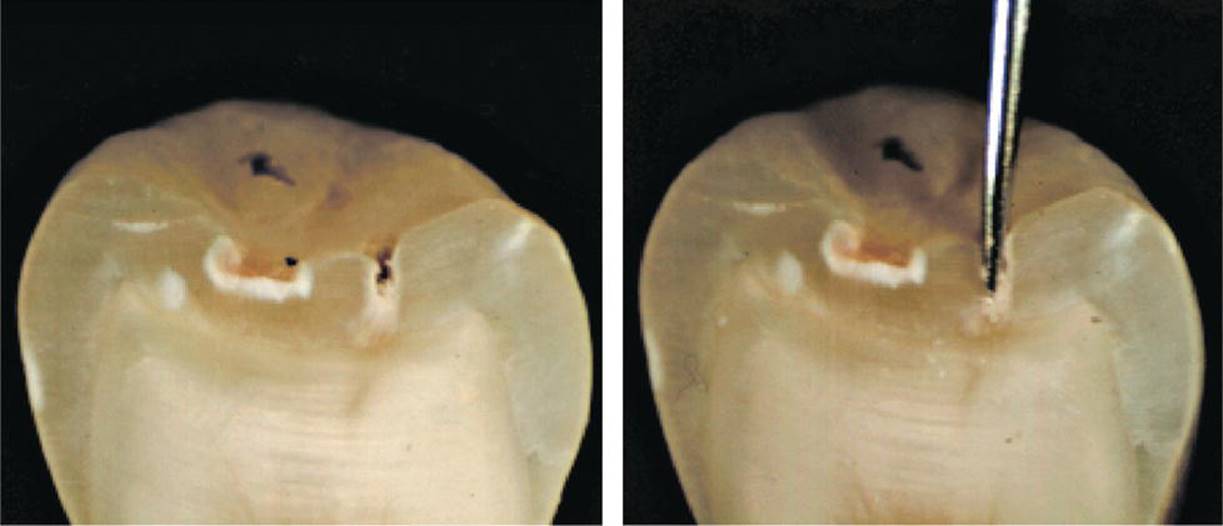

Occlusal surfaces (pit and fissures)

Particularly in pits and fissures, the probe should be used carefully in order to avoid iatrogenic damage (Figure 12.4). The probe is an important tactile aid and may be necessary to remove plaque. However, solely visual assessment of early (noncavitated) fissure caries lesions is not improved by probing [10]. In this context it is important to recognize that even if the probe “catches,” this does not necessarily mean that there is a soft lesion.

Figure 12.4 Sectioned premolar with an enamel caries lesion in the fissure before probing (left). Intense probing (right) destroys the surface zone of the lesion.